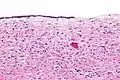

Serous cystadenomas are diagnosed by histomorphologic examination, by pathologists. Grossly, they are, usually, small unilocular cysts that contain clear, straw-coloured fluid. However, they may sometimes be multilocular. Microscopically, the cyst lining consists of a simple epithelium, whose cells may be either:[3]

- be columnar and tall and contain cilia, resembling normal tubal epithelium

- be cuboidal and have no cilia, resembling ovarian surface epithelium